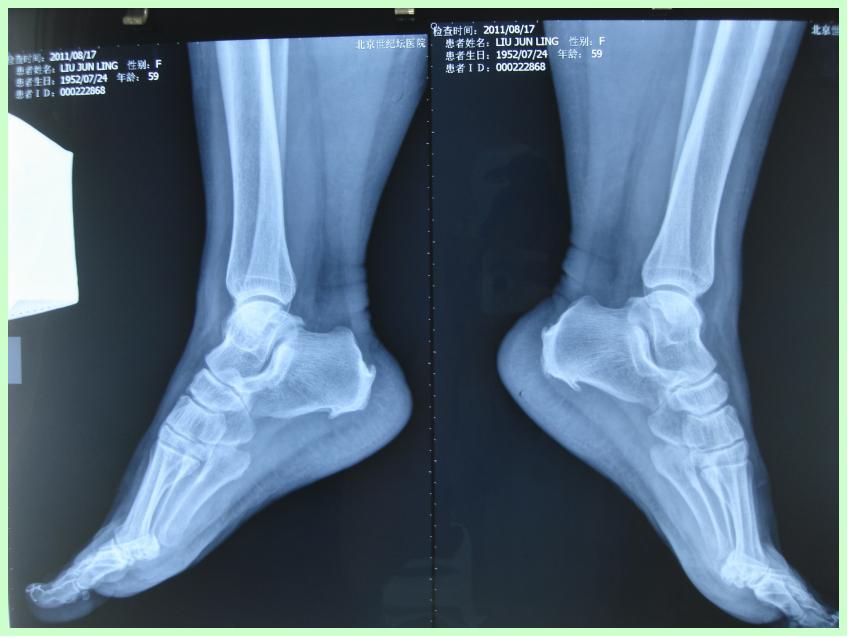

检查:左足跟部侧位X光片

诊断:左脚跟骨骨刺